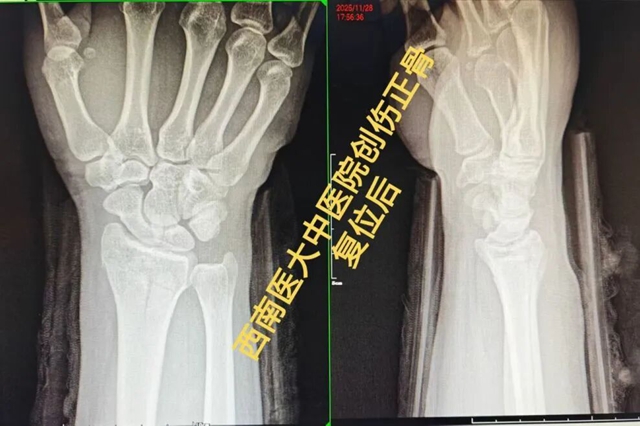

事故发生后,黄先生被紧急送往就近医院就诊。影像检查结果清晰显示:右侧桡骨远端粉碎性骨折。医生当即给出手术治疗的建议,但一想到要开刀、留疤痕,术后还要经历漫长的恢复期,黄先生满是抗拒。

接诊的张小敏主治中医师接过黄先生的检查报告后,细致分析骨折移位情况,又耐心为黄先生进行了详细查体。“关节面粉碎,手法复位有难度,但是我们仍然可以通过牵引的方式恢复关节塌陷,再采用拽、按等手法恢复桡骨高度和关节面平整。” 张小敏用温和的语气瞬间缓解了黄先生的紧张情绪。

“太神奇了!现在手腕一下子就不那么胀痛了,也能轻微活动了!” 黄先生当场惊喜地说道。后续复查显示,黄先生骨折复位良好,经过一段时间的康复锻炼,黄先生的手腕功能逐渐恢复正常,重返工作岗位。

张小敏主治中医师介绍:桡骨远端骨折在临床中较常见,大多数桡骨远端骨折通过中医正骨疗法保守治疗,可以取得很好的效果。如果不幸遭遇桡骨远端骨折,不妨试试中医正骨这一传统而有效的治疗。

中医正骨疗法是通过拔伸、复位、对正等手法,采用小夹板外固定方式,辅以中药外敷、针刺消肿止痛、手法理筋、传统练功及现代康复等,治疗各种骨折、脱位及急慢性软组织损伤等运动系统疾病的一种治疗方法。